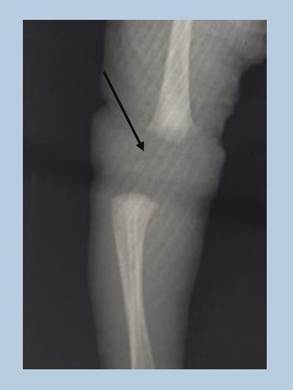

Figura 2. Estudio radiológico del caso donde se observó una luxación tipo III.

En las primeras horas luego del nacimiento, se realiza radiografía de rodilla que confirma la luxación de rodilla (figura 2).

Las luxaciones pueden clasificarse de acuerdo a sus características clínicas y radiológicas. La clasificación Laurence y Curtis Fischer se subdivide en: tipo I o recurvatum grave de la rodilla, tipo II o subluxación de la tibia sobre el fémur y tipo III o luxación completa de rodilla, tal como se observa en el caso clínico descrito Leveuf y Paris clasifican la deformidad en tres grupos (5,7) (figura 4).

En la paciente analizada el diagnostico se confirmó en las primeras horas de vida mediante la observación clínica y la radiografía simple lo que permitió iniciar medidas terapéuticas precoces (8).